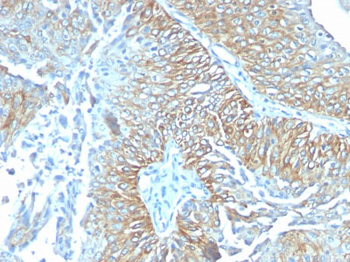

| Description | TRIM29 (Lung Squamous Cell Carcinoma Marker); Clone TRIM29/1041 (Concentrate) |

| Application notes | A431 cells. Tonsil or Squamous cell carcinoma. |